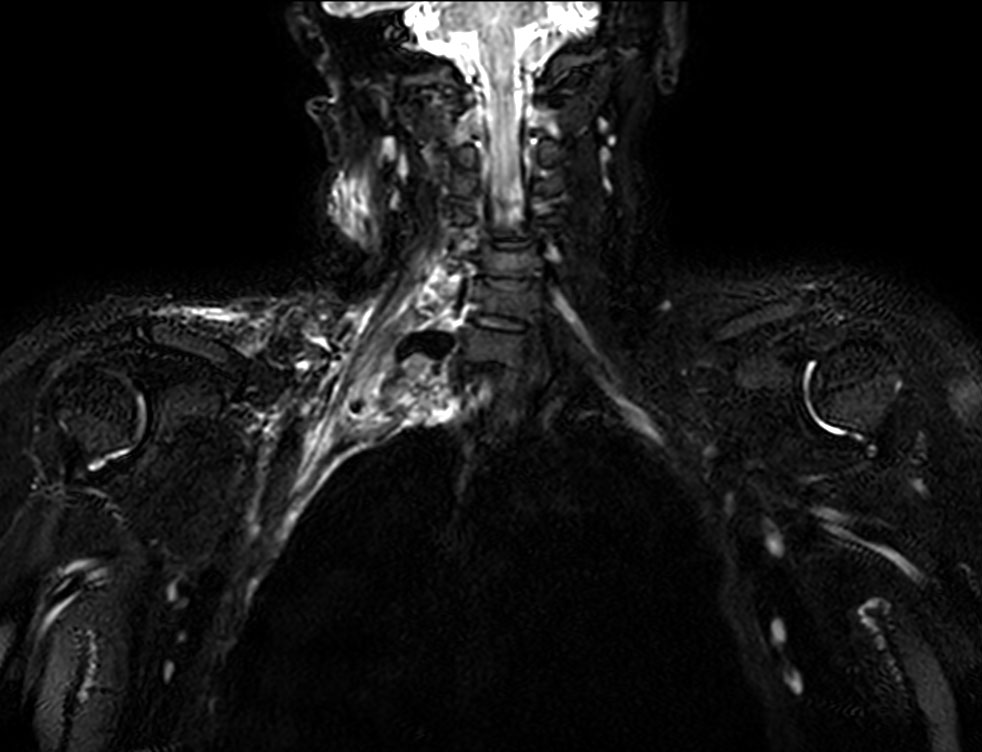

Patient referred to MRI post trauma of the HeadNeck region.

Coronal STIR TSE